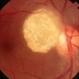

- tuberous sclerosis

- Mulberry lesion.